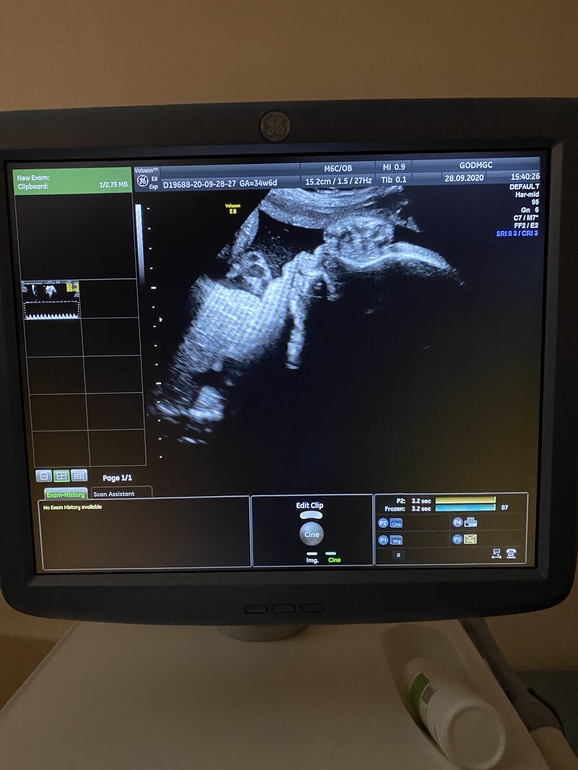

Прошли 3 скрининг, снова кровоток не очень(

С малышкой все хорошо, вес 2300, 2 недели назад была 1870, растём)

В головном, обвития нет. Срок по узи 33,6.

Кровоток в пуповине 2 недели назад был 0,62, сегодня 0,70 при границе нормы 0,73.

Узистка моя сказала, что малышка набирает по сроку, значит просто надо и дальше мониторить каждые 2 недели. Но и Дипиридамол не помешает.

На фото ладошку сверху положила) и губки бантиком сделала)))